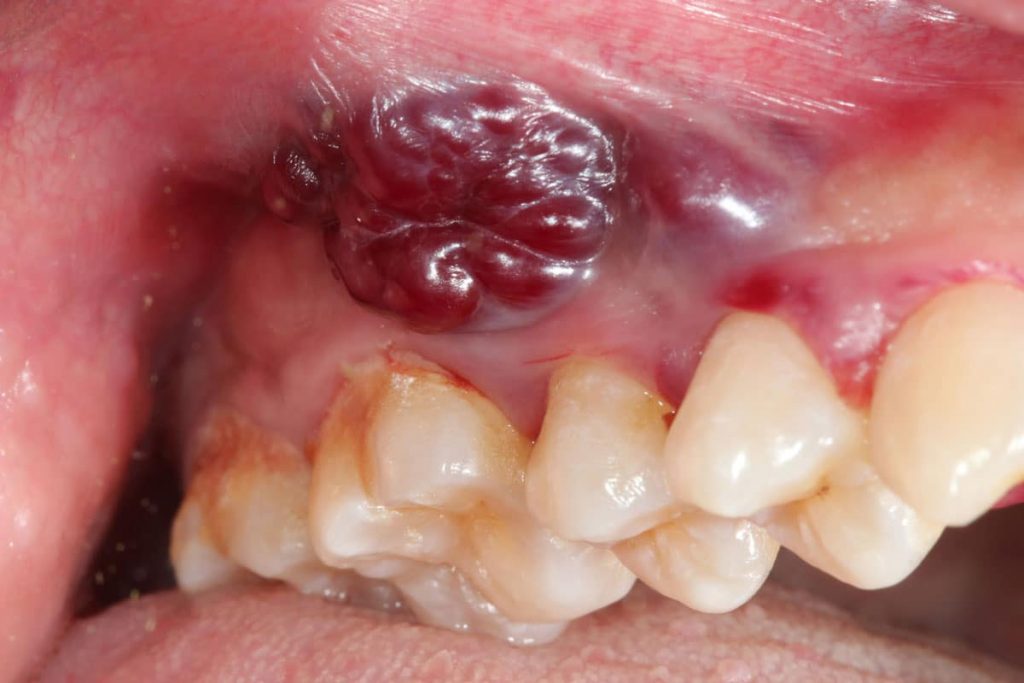

Questa crescita può inizialmente essere molto piccola e poco evidente, ma con il tempo può espandersi e coinvolgere i tessuti circostanti. Le aree più frequentemente interessate sono la lingua, il pavimento della bocca e le gengive, anche se nessuna zona è completamente esclusa.

Col passare del tempo, queste cellule alterate possono diventare sempre più numerose e formare una lesione visibile. In una fase iniziale può trattarsi di una macchia o di una piccola ulcera che non guarisce. Se non individuata e trattata, la situazione può evolvere verso una forma più seria.

Uno degli aspetti più importanti riguarda la capacità di riconoscere i segnali precoci. I tumori del cavo orale, nelle fasi iniziali, possono manifestarsi con sintomi apparentemente innocui.

Una piaga che non guarisce, una macchia bianca o rossa, un ispessimento della mucosa o una sensazione persistente di dolore possono essere segnali da osservare con attenzione. Anche difficoltà nella masticazione o nel parlare meritano un approfondimento, soprattutto se persistono nel tempo. Intervenire precocemente aumenta in modo significativo le possibilità di trattamento efficace.